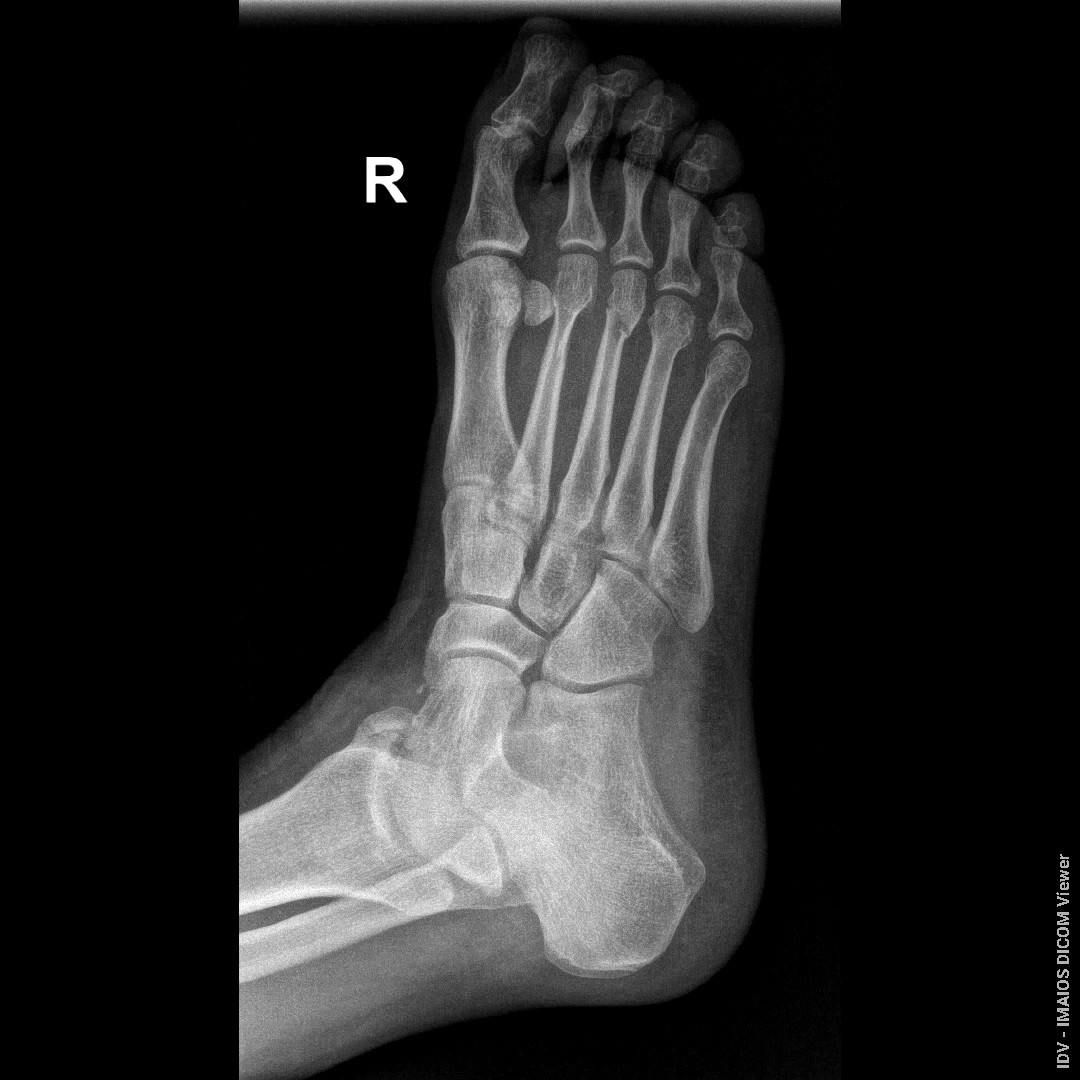

Здравствуйте, доктор, переломы были 23.06.2025, прошло уже почти 7 недель, возможно ли судя по снимкам образования ложных суставов, если будет срастаться плохо? прикрепляю последние снимки от 08.08.2025

Здравствуйте. Ложный сустав за 7 недель не формируется, на снимках есть признаки сращения, но перелом ещё не полностью зажил, поэтому нужен щадящий режим и контроль у травматолога.

Андрей Павлович, Большое Спасибо Вам за ответ! Я понял, что за 7 недель ложнвй сустав не формируется, но если переломы так до конца и не срастутся, возможно ли формирование ложных суставов? На приложеных снимках есть два первичных снимка от 23.06.2025 и один с5имос вчерашний, от 08.08.2025

Да, при отсутствии сращения со временем возможно формирование ложного сустава, поэтому важно наблюдаться у травматолога и контролировать процесс заживления.